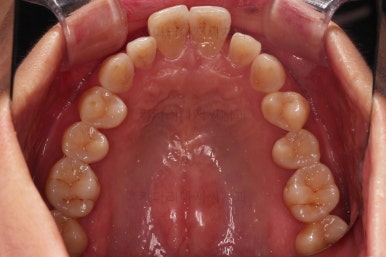

초진 시, 입안의 모습이에요.

"최근 들어 점점 틀어지고, 점점 튀어나오고, 점점 사이가 벌어져요."

성장이 끝난 성인들은 해가 갈수록 특히 아래앞니가 삐뚤어지는 것은 자연스러운데요.

이번 환자분의 말씀대로 최근에 변하가 심하게 나타난 경우는 원인이 딱 하나에요.

잇몸(치주)

흔히 풍치라고 하죠.

전반적인 잇몸이 나빠진다 -> 어금니가 씹는 힘에 버텨주지 못하고 앞으로 쓰러진다. -> 앞니가 강하게 부딪히며 아래앞니가 윗니를 앞으로 쳐낸다. -> 돌출입이 생기고, 앞니 사이 틈새가 생긴다.

앞니가 튀어나오고 틈새가 생기는 것이 결과이긴 하지만 원인은 어금니쪽 잇몸에서부터 찾아야해요.